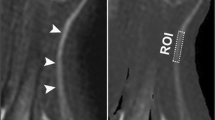

where S0 and S1 represent the signal intensity without and with off-resonance saturation pulse, respectively. MTR was first calculated separately for each image slice whereby only the ten central image slices of each image stack were included into analysis to avoid artifacts or inhomogeneities caused by the B1 field. Values were then averaged to obtain a mean value for each patient. The process of image coregistration is illustrated in Fig. 1.

Process of nerve segmentation and image coregistration. a Manual segmentation of the sciatic nerve was performed on an axial T2-weighted sequence with spectral fat-saturation (T2w) of the right thigh. Regions of interest were then coregistered with magnetization transfer ratio (MTR) sequences with (b) and without (c) off-resonance saturation pulse